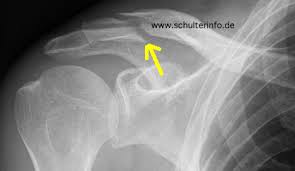

Hier muss dann bei Beschwerden eine aufwendige Korrekturoperation erfolgen. Sogar inklusive des eingesetztem Draht. In manchen Fällen macht der Schlüsselbeinbruch aber eine Operation notwendig zum Beispiel wenn gleichzeitig die unter dem Schlüsselbein liegenden Blutgefäße oder Nerven verletzt oder die Knochenbruchstücke stark verschoben sind.

Die Reposition der Fraktur dh. Eine teilweise Metallentfernung am Sprunggelenk findet etwa sechs Wochen nach der Haupt-OP statt. Dauer der Therapie einer Schlüsselbeinfraktur Die Gesamtdauer der Therapie beträgt in der Regel 6-8 Wochen bei problemlosen Verlauf.

Nach rund 10 bis 15 Monaten sollte noch einmal eine Röntgenaufnahme durchgeführt werden und in diesem Zeitraum sollte mit dem behandelnden Arzt die Frage der Plattenentfernung erörtert werden.